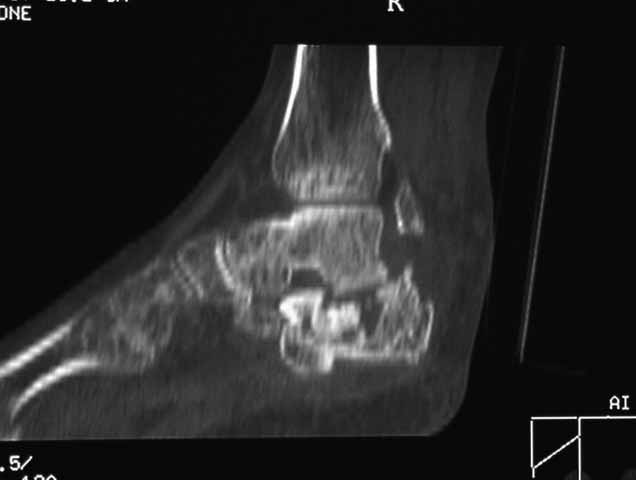

КТ перелома пяточной кости Пациент 60 лет с производственной травмой-закрытые переломы правой пяточной кости, тибиального плато слева поступил в феврале с.г. На 4 сутки выполнена открытая репозиция, остеосинтез внутрисуставного перелома голени, ручная репозиция пяточной кости. Через три месяца начал ходить с нагрузкой на обе ноги. Консолидация голени с полным восстановлением функции колена. Правая стопа умеренно отечна, продольно распластана, длительная ходьба вызывает боли и увеличение отека. Прошел несколько курсов ударно-волновой терапии, грязелечение, боли и отек уменьшились. В наших планах -оформление на ВТЭК, через год возможно выполнение подтаранного артродеза.Но после производства КТ в августе появились сомнения в консолидации перелома.Ранее у нас не было опыта КТ переломов стопы и сканы привели в замешательство.Прилагаю снимки со дня поступления, августовские пациентом не представлены.С благодарностью примем советы коллег.

Данное исследование сделано в неправильной позиции стопы, стопа находится под прямым углом. Но несмотря на это, здесь можно увидеть, что латеральная стенка смещена, фиброз между фрагментами и варусное смещение пятки.

Топография зависит от позиции пятки в пространстве и неправильное положение закрывает обзор нужных структур. Важными структурами в исследовании пятки является задняя фасетка, бугор и боковые стенки. Существует специальные рентгенснимки, показывающие импинджмент с лодыжкой, а также положение бугра. Для КТ стопу надо инклинировать под 30 градусов, иначе можно пропустить важные переломы.

Нет срочности, но необходимо исправить варус и сделать субталарный артродез. Латеральное положение, расширенный доступ и closed wedge остеотомия с открытым кнаружи углом, возможно, удастся визуализировать через линию остеотомии недостающие части медиальной стенки - костный графт. Дистракция и после подготовки поверхности кости субталарный дистракционный артродез с помощью костного блока, взятого из крыла. Достаточно двух 6.5мм канюлированных шурупов из пяточного бугра медиально и латерально в направлении таранной кости. Из-за увеличения высоты стопы после артродеза кожа закрывается трудно, и могут быть краевые некрозы, которые лечатся долгими перевязками. Нужна предоперационная беседа по поводу задержки заживления, тогда больные встречают проблемы с пониманием.